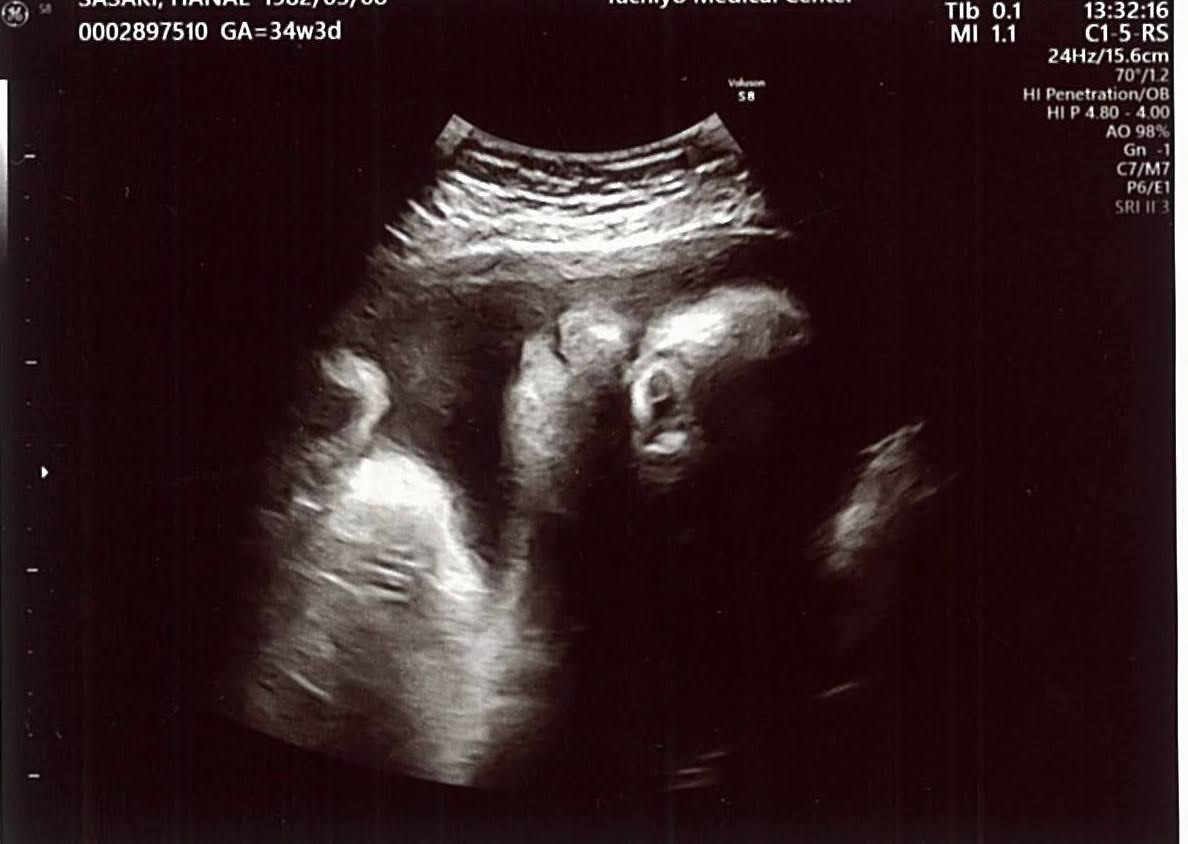

さて、われらのベビーです↓(エコー写真あり)

<前回>→<今回>

AC 268.4mm→FL/AC 23%

FL 60.7mm→64.7mm

EFW 1990g→2311g

BPD 85.9mm→FL/BPD 73%

表記がいくつか%に変わっていて良く読み取れないのですが、重さはやはり2000gを超えました!!エコーみてるとやっぱりエイリアン(笑)。あと1ヶ月で1kgも増えると思うと、最後の成長っぷりはすごい!